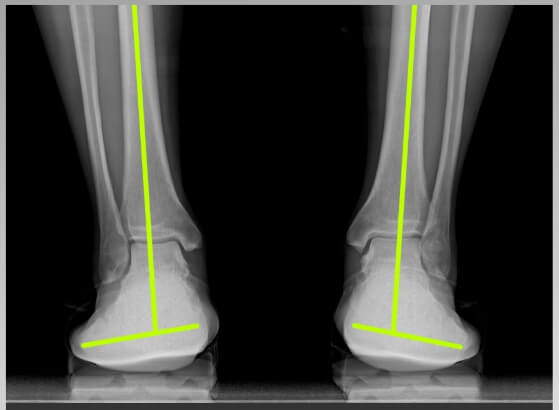

보통 푹신한 신발이 편할 것 같지만 오래 신으면 오히려 발 아치가 무너져 체중을 지탱할 때 발이 쉽게 피로해지고 관절, 근육, 인대에 무리를 준다고 합니다. 하지만 골 스튜디오 그래비티 밸러스의 단단한 미드솔은 아치가 지지 않도록 받쳐주어서 발과 무릎 골반의 부담을 감소시키며 발 피로해소에 도움을 줍니다. 부드러운 아웃솔의 쿠션감이 체중의 2배~ 2배에 달하는 하중과 지면의 충격이 발과 관절에 전달되지 않게 완충하는 역할을 합니다.

그래서 저처럼 발 아치가 무너진 분들이나 또는 다리가 평소보다 많이 나가는 체중을 받쳐줘 하는 임산부들에게도 도움이 많이 된다고 합니다. 리뷰를 살펴보니 회사 실내화용, 임산부용 외에도 무지외반증이나 발가락관절염을 앓고 있는 분 등 발이 편해야 할 분들도 많이 추천하고 있더라고요.